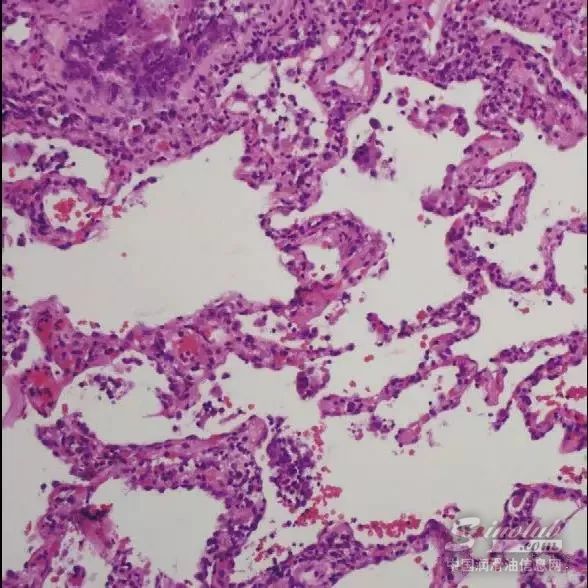

1992年,一家汽车零部件厂的许多工人被诊断为过敏性肺炎,这是对微生物过敏反应造成的肺部疾病。这一事件引起了人们对金属加工液微生物研究的浓厚兴趣。

1992年至2000年期间,整个金属加工行业报道了约250个HP病例。而不变的是,HP是群发疾病,在某一工厂中就有四到四十个病例。从金属加工液中回收的超过12种不同类型的细菌和真菌会诱发HP。